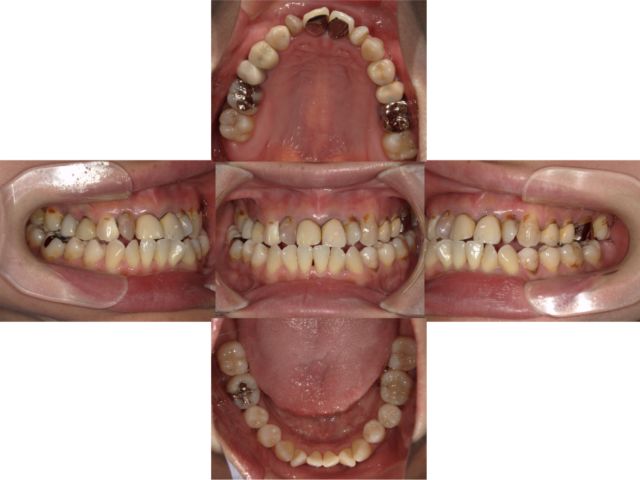

Before

主訴 歯を入れたい、前歯を綺麗にしたい 診断名 右下欠損、審美障害、カリエス 年齢・性別 40代・男性 治療期間・回数 約1年3ヶ月・約20回 治療方法 インプラント、オールセラミッククラウン、ホームホワイトニング、カリエス治療 費用 ¥400,000(インプラント)+¥396,000(前歯部)+¥40,000(ホワイトニング)+保険診療 デメリット・注意点 インプラント:歯周炎になる可能性があります 破折、2次カリエスの可能性があります -